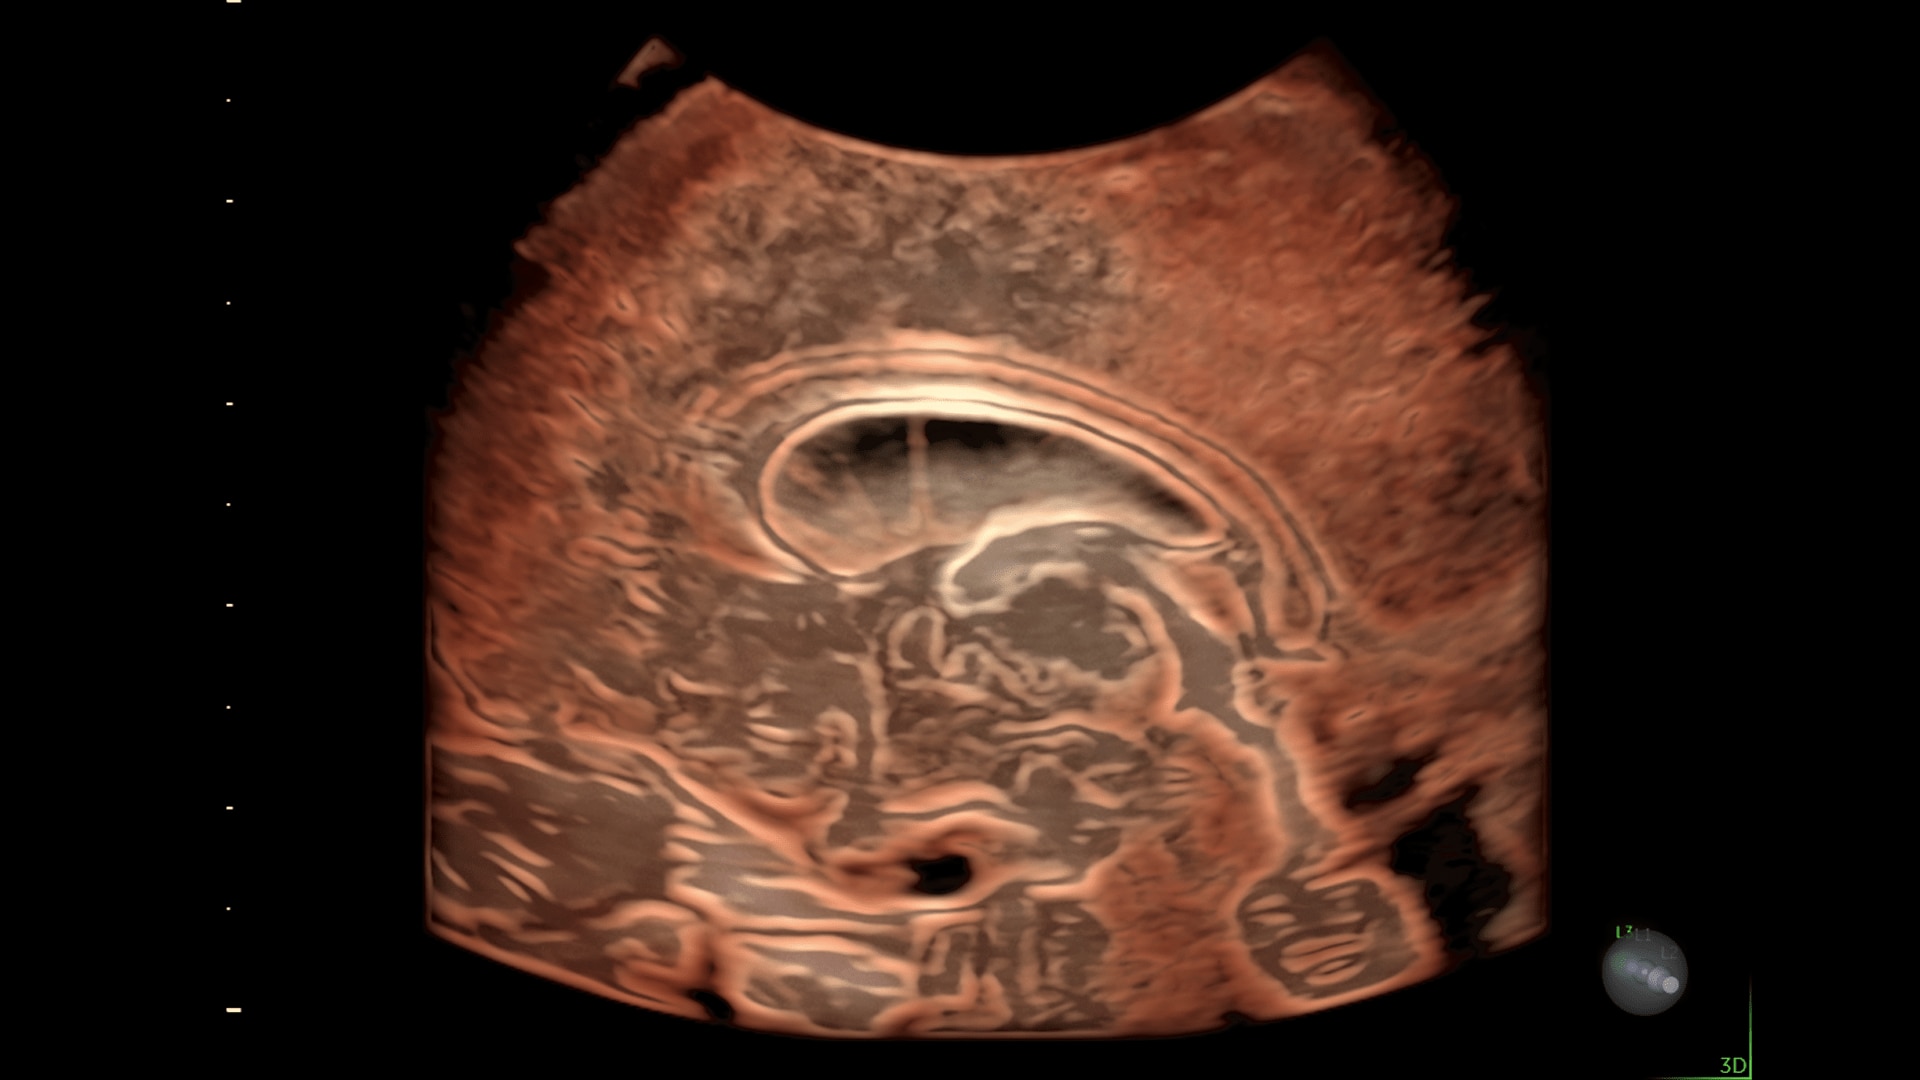

Enhanced Volume Imaging

Deliver next generation 3D/4D & Color images with HDlive Studio+